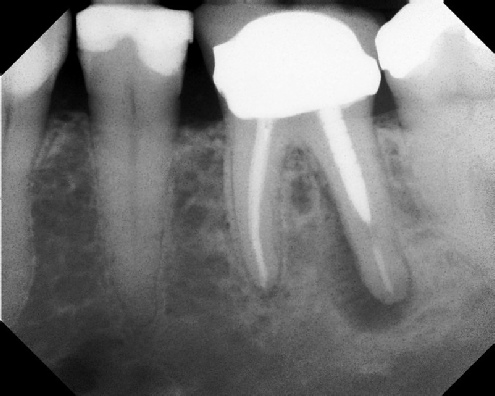

Root Canal Retreatment - Meriden 8 mos. recall Post-op Pre-op